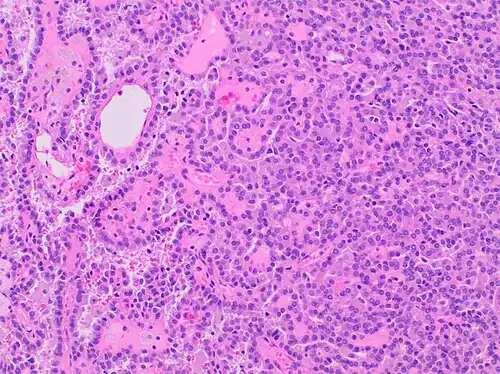

| Papillary renal cell carcinoma, type 1, characterised by tubulopapillary architecture with admixed foamy histiocytes in the papillary cores. | |

Type 1 PRCC, also known as a renal tumor caused by a genetic predisposition of hereditary papillary renal cancer syndrome, compromises approximately 25% of all PRCCs.[14][15] In the perspective of immunochemistry, it has a profile of strong CK7 and alpha-methyl acyl-CoA racemase (AMACR) expression at most focal CA-IX expression.[16] Histologically, its epithelium is composed of relatively small-sized simple cuboidal cells lined in a single layer.[17] These cells are well-characterized by basophilic cytoplasm.[18] Due to its solid growth, an extremely compact papillary architecture is often observed.[16] Other morphological characteristics include intracellular hemosiderin and foamy macrophages placed inside of papillary fibrovascular cores or psammoma bodies.[19] In general, the nuclei of type 1 PRCC belong to grade 1-2 of the Fuhrman system.[16]

![A micrograph of type 1 PRCC, illustrating features of small basophilic cells with scarce cytoplasm. A single layer of cells are surrounding the basal membrane.[20] Foamy macrophages are inside of papillary fibrovascular cores.](./_assets_/Histopathology_of_papillary_renal_cell_carcinoma_type_1%252C_high_magnification.jpg) A micrograph of type 1 PRCC, illustrating features of small basophilic cells with scarce cytoplasm. A single layer of cells are surrounding the basal membrane.[20] Foamy macrophages are inside of papillary fibrovascular cores.

A micrograph of type 1 PRCC, illustrating features of small basophilic cells with scarce cytoplasm. A single layer of cells are surrounding the basal membrane.[20] Foamy macrophages are inside of papillary fibrovascular cores. -